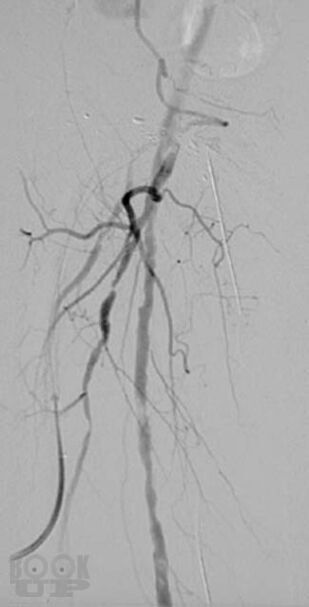

В атласе представлены более 1200 цветных иллюстраций по всем основным патологическим процессам, с которыми можно встретиться на практике, а также при изучении курса патологии или при подготовке к квалификационному экзамену по медицинским специальностям, проводимому в США (USMLE). Принцип построения атласа соответствует главам 7-го издания руководства «Основы патологии болезней Роббинса и Котрана» (Robbins and Cotran Pathologic Basis of Disease). Иллюстрации данного атласа дополняют рисунки, представленные в этом руководстве. В атлас включены иллюстрации наиболее важных рентгенологических изменений, которые отражают реальные клинические проявления при конкретных заболеваниях. Высококачественные иллюстрации имеют маркировку для определения ключевых признаков патологических изменений. В каждом наблюдении представлено комплексное описание ключевых морфологических признаков, а также клинико-лабораторные данные по наиболее важным разделам патологии. Картины макроскопических и микроскопических изменений дополнены цветными рисунками и схемами, а также соответствующими рентгенограммами. Атлас является прекрасным изданием, содержащим необходимый объём сведений или справочных материалов для читателя, имеющего различный уровень подготовки, — студента, врача, научного работника.